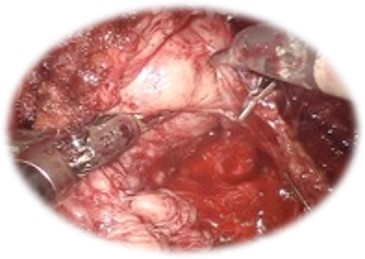

Nefrectomia parțială robotică:

• Presupune îndepărtarea procesului tumoral cu păstrarea parenchimul renal sănătos

• Oferă:

• Spitalizare scurtă, cu reintegrare socio- profesională rapidă

• Sângerare redusă

• Risc scăzut de complicații intra/ postoperatorii

• Comparativ cu chirurgia laparoscopică, abordul robotic permite scăderea timpului de ischemie.